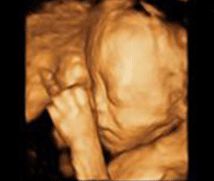

• -郑州万安妇产医院

相册

巴啦啦小魔仙 上传于 18-10-25 | 报错